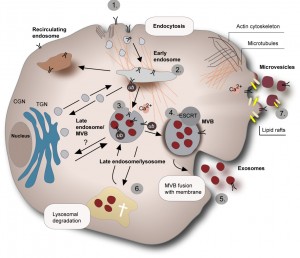

Exosomer är små virusliknande partiklar som transporterar genetiskt material och signalsubstanser från en cell till en annan. En forskargrupp vid Lunds universitet har nu funnit en typ av exosom som släpps ut från allvarliga hjärntumörer,…